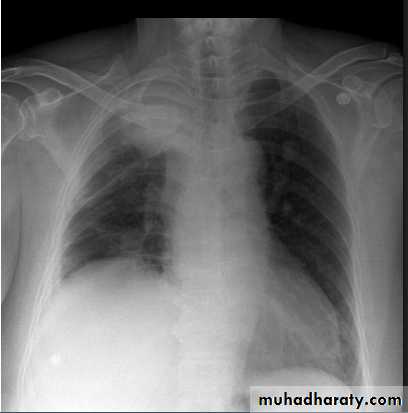

Pleural Effusion on Chest Radiographs.

Posteroanterior (A) and lateral (B) chest radiographs demonstrate the typical meniscoid appearance (arrows) in a patient with a left pleural effusion